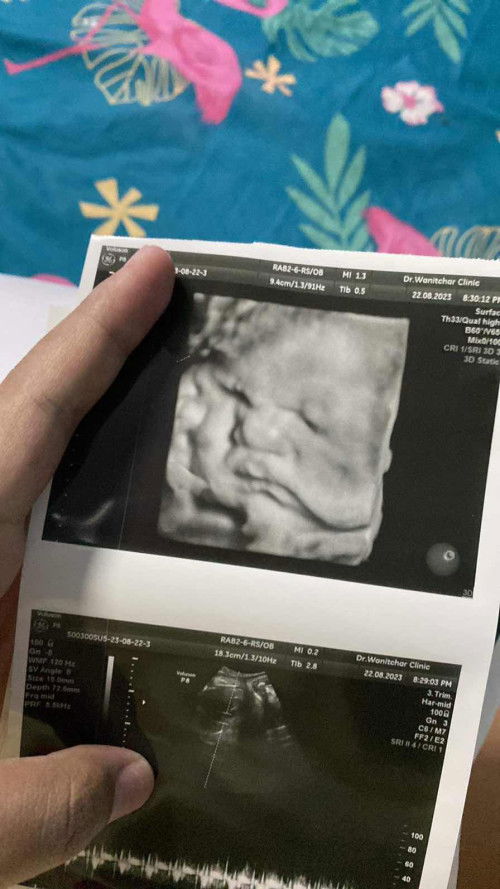

#ขอคำแนะนำหน่อยค่ะ #คุณแม่ๆช่วยแนะนำหน่อยค่ะ วันนี้ไป อัลตราซาวด์มาแร้วคุณหมอบอกว่ากระเพราะอาหารน้องเล็ก คุณหมอบอกให้ทานน้ำเยอะๆเพื่อดูรอบหน้าเสี่ยงจะเป็นอะไรไหมค่ะกังวรมากเลยค่ะมีใครเคยเป็นไหมแม่ได้ยินแบบนี้แม่กังวล😔🥺